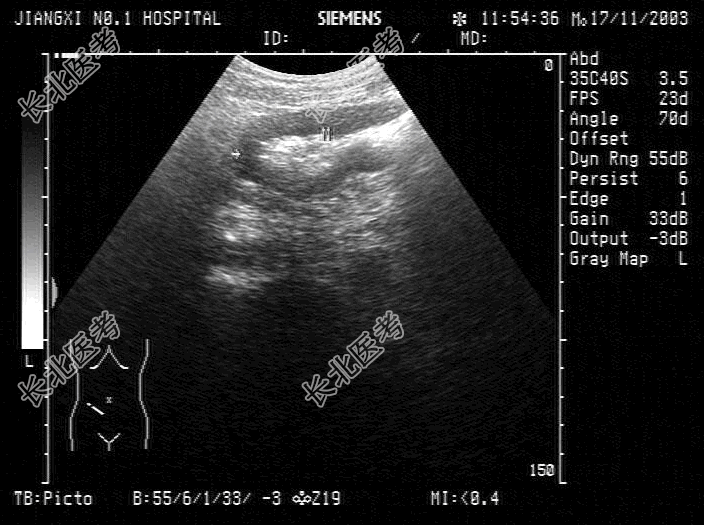

- 单项选择题患者,男, 右下腹有压痛,时有腹泻。结合超声检查如图, 诊断是

A、阑尾脓肿

B、结肠癌

C、肠梗阻

D、肠结核

E、溃疡性结肠炎